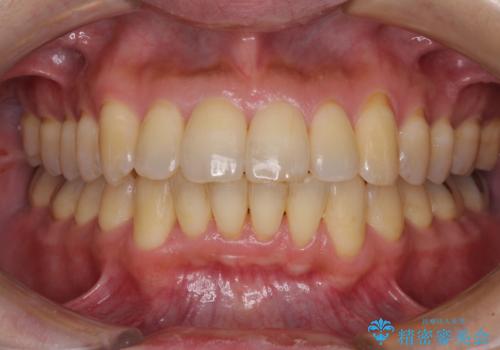

前歯のデコボコ ワイヤー装置での短期間治療

- 治療期間

- 1年3ヶ月

治療開始の頃は、食事や歯磨きが慣れず、装置が頻繁に脱落しましたが、2,3ヶ月ほどで慣れ、その後は1年ほどで治療を終えることができました。